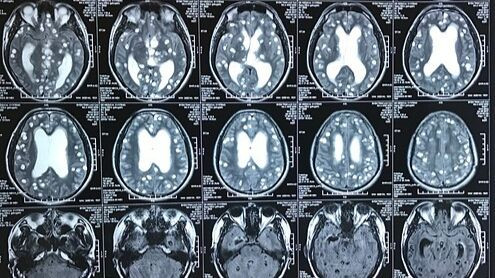

Ảnh minh họa tổn thương não do ổ sán não.